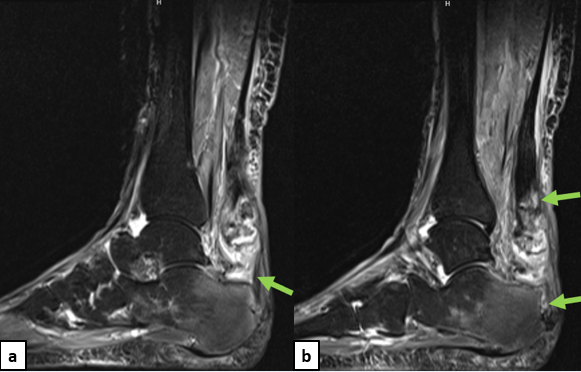

A healthy 66-year-old female who presented at our office via urgent care referral for a chronic left Achilles tendon rupture. She had been diagnosed by an another provider with Achilles tendinitis with retrocalcaneal spurring (Figure 1a) several months prior and had been working with physical therapy. She presented to urgent care with concern for possible deep vein thrombosis (DVT) as she experienced worsening calf pain while trying to walk for the previous couple of weeks. She had no recollection of a provoking injury, so the exact timing of rupture is unknown, but it likely took place about 7 weeks prior. Urgent care obtained updated radiographs and a magnetic resonance imaging (MRI) study (Figures 1b & 2).

The patient presented to our office with a palpable dell of the Achilles tendon extending from the insertion site to the mid-calf region. There was no plantarflexion with calf squeeze and the patient had a positive Thompson’s test. The patient elected to move forward with surgical intervention consisting of a flexor hallucis longus tendon transfer and open repair of the Achilles tendon rupture with bone-tendon allograft and remodeling of the posterior calcaneus.

This case report details the surgical procedure performed for a patient suffering from chronic underlying retrocalcaneal exostosis pathology. This patient subsequently developed an Achilles tendon rupture with initial misdiagnosis. The technique described allows the surgeon to restore the Achilles tendon while augmenting the strength of repair with subsequent FHL transfer, avoids donor site morbidity, and addresses the weakness of the posterior musculature group. We find this technique especially advantageous for chronic Achilles ruptures involving a substantial portion of the distal tendon segment, and we add internal fixation to help stabilize the allograft bone for incorporation into recipient bone.